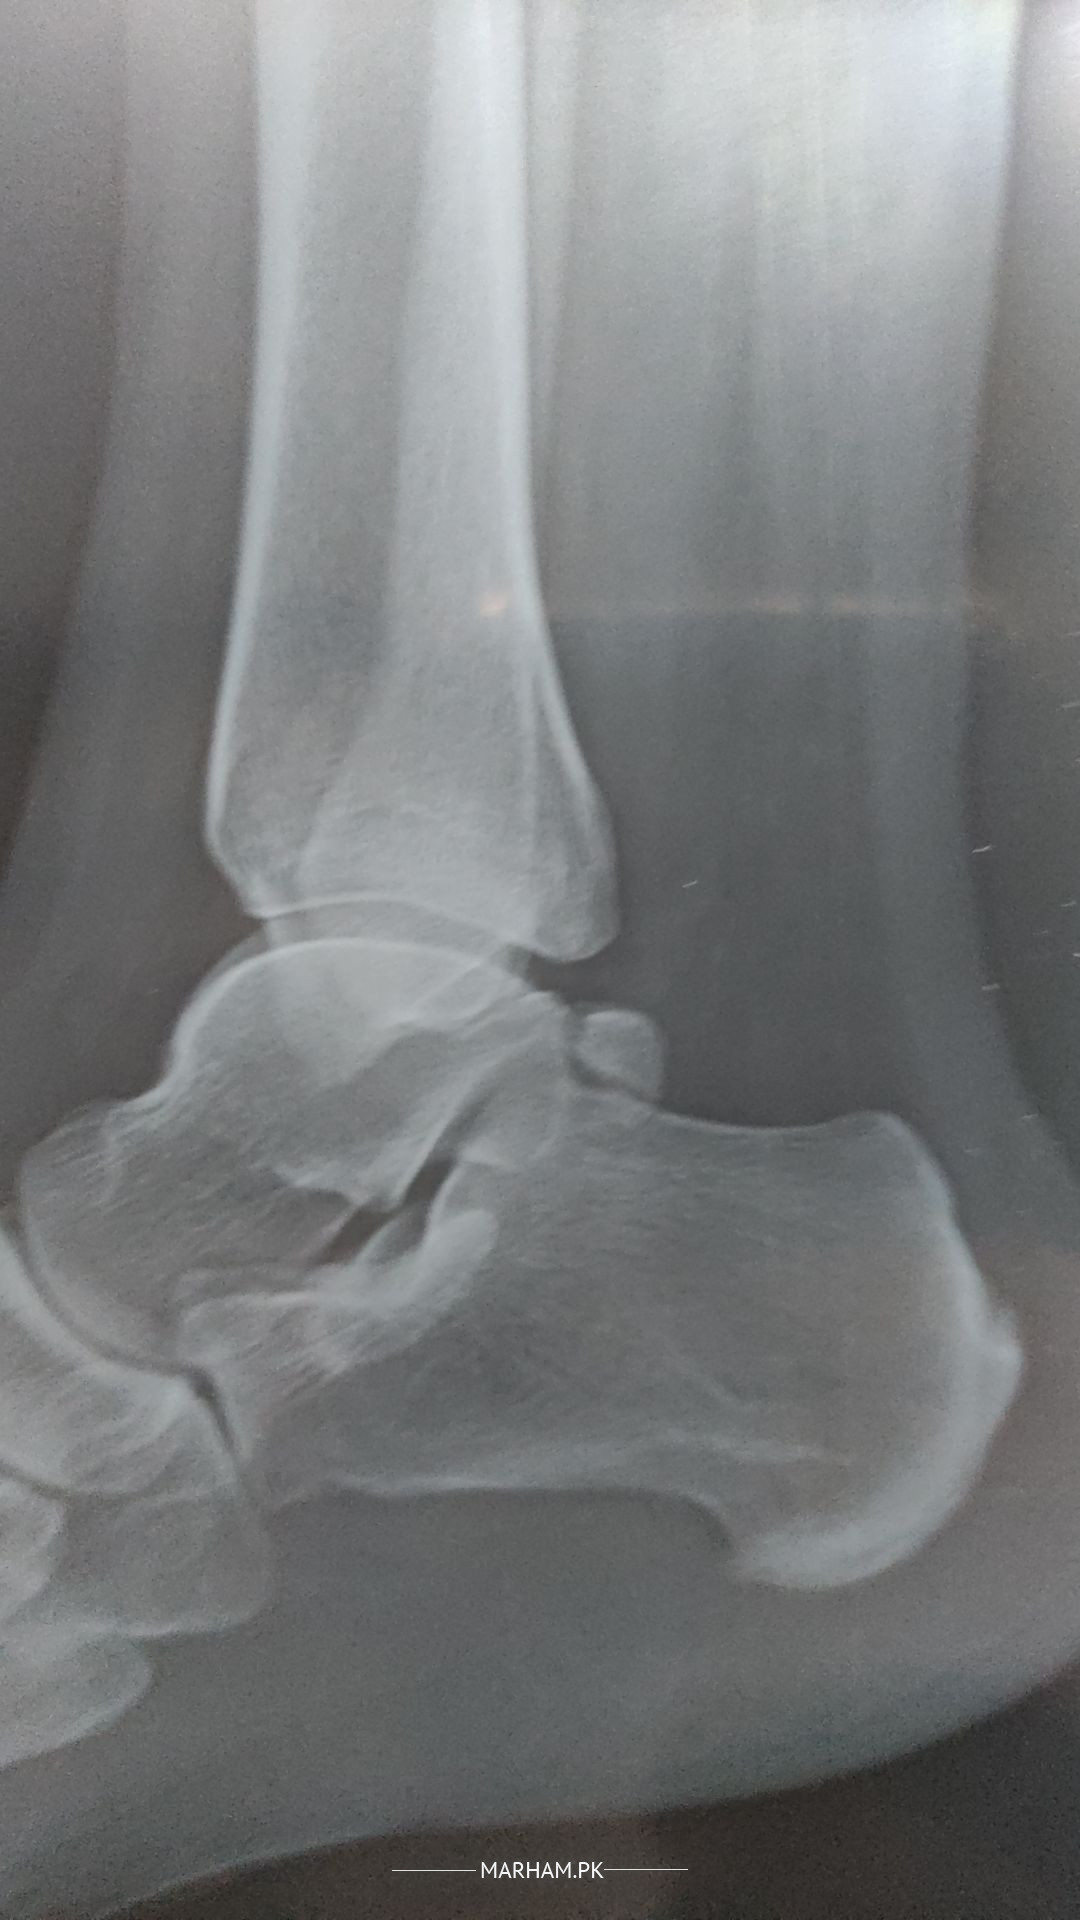

Hi I have lain in front ankle and in the vein. dr prescribe me with the medcines i have attached in this. i have also attached my xray what would be the issue. i feel uncoomfortable feeling in the vein as well. can you tell me what the issue might be.

Attach Photo here: